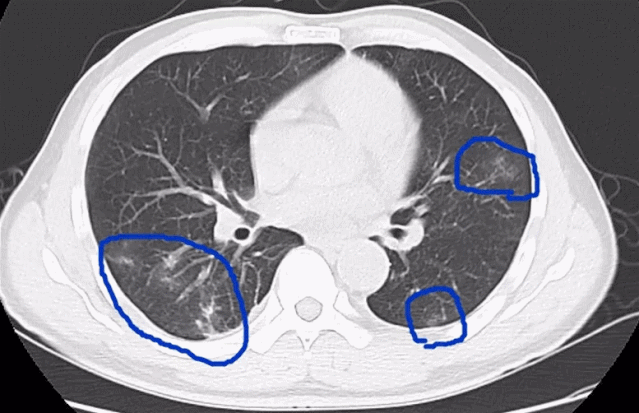

在医院检查发现,3人的血常规中嗜酸性粒细胞明显升高。经过寄生虫抗体、CT等检查,他们都被诊断为「肺吸虫病」。